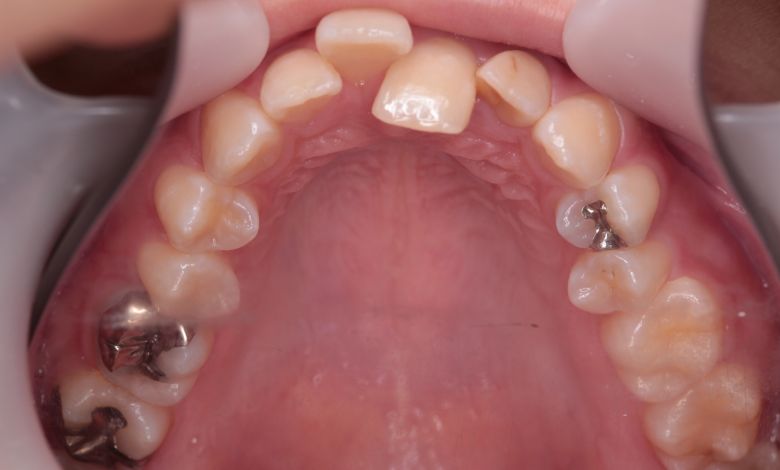

上下顎ともに犬歯が唇側に大きく突出しており、歯列弓が狭小なため、

他院では上下左右4本の便宜抜歯を前提とした矯正治療を提案されていました。

上顎には左右の犬歯が著しく唇側に偏位している

精密検査の結果、当院では抜歯を行わず、歯列弓の拡大によってスペースを確保し、非抜歯での矯正治療を選択しました。歯列の叢生(ガタガタ)は解消され、機能的かつ審美的に優れた咬合が得られました。